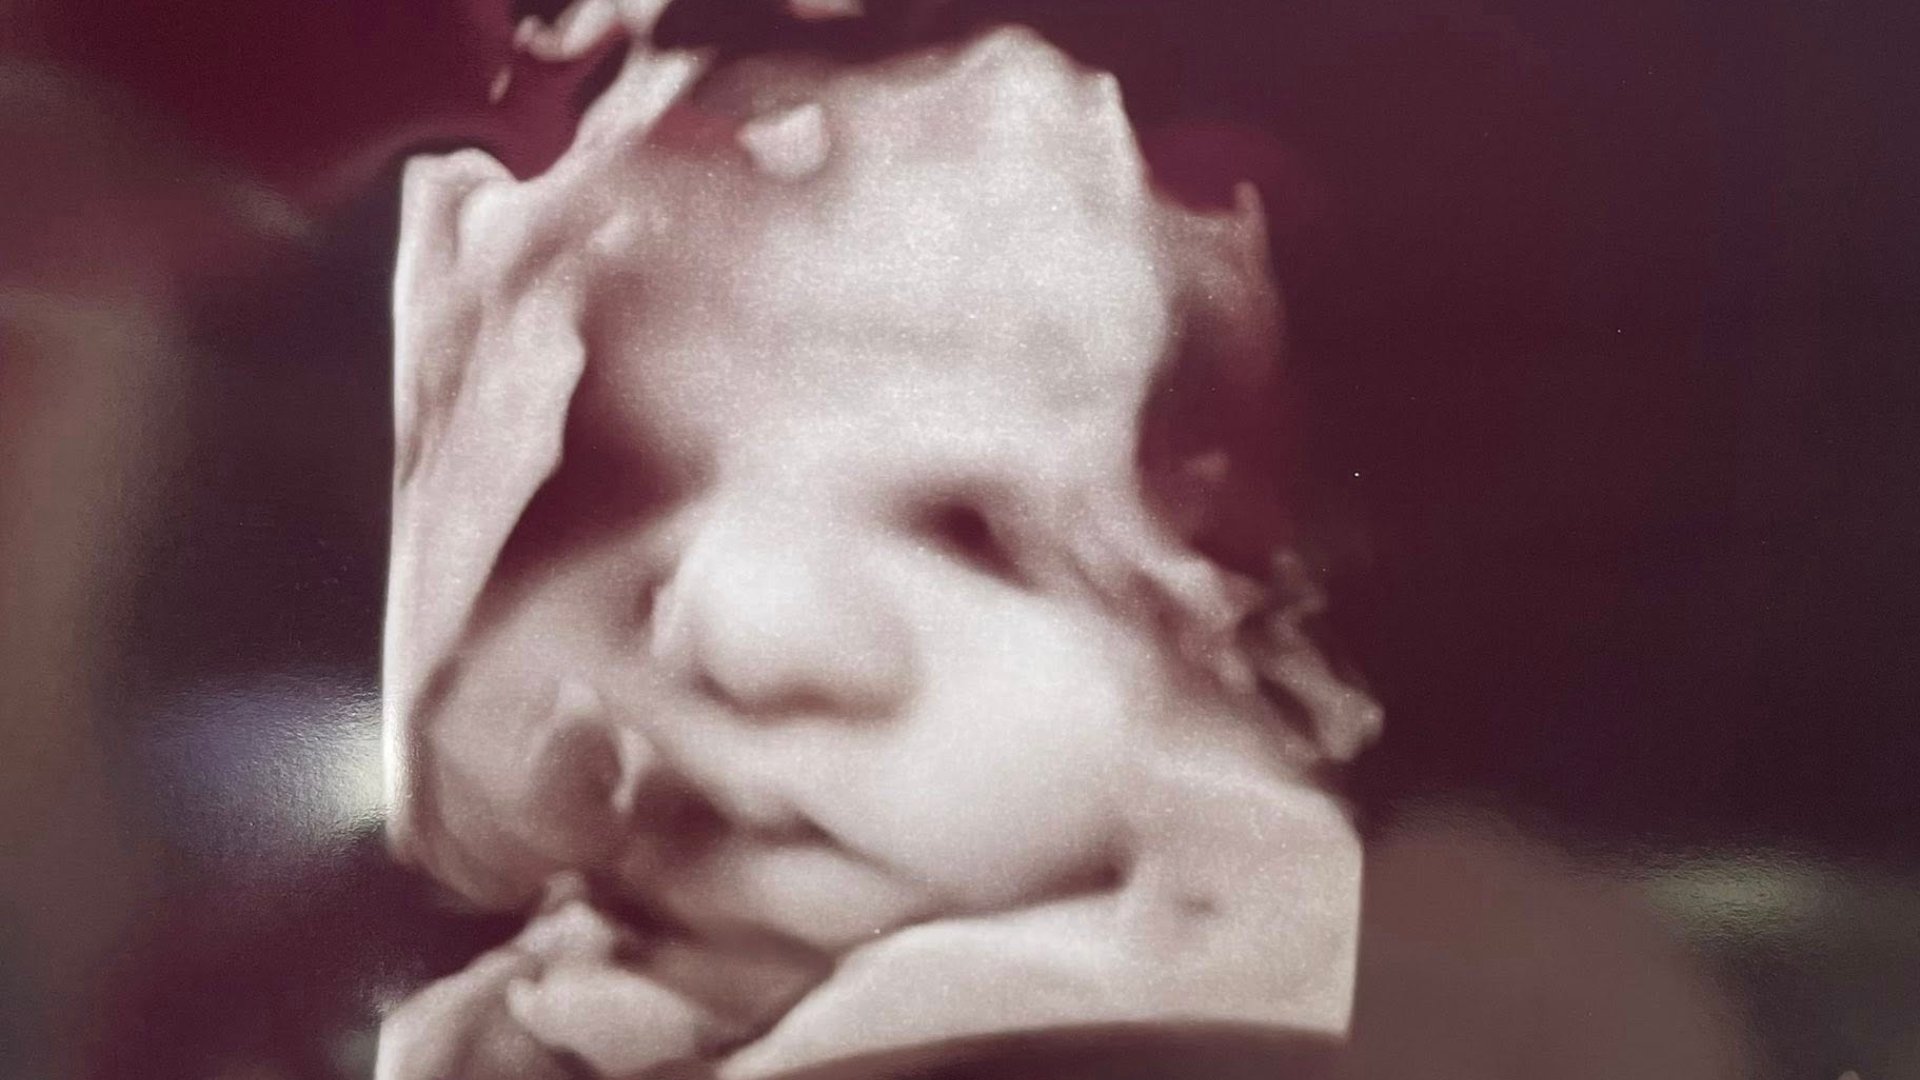

The 32-week scan appeared to show a large hand caressing the head of the unborn baby in the mother’s womb. The visible answer to her prayers happened to Amanda Foster, 33, who was eight months pregnant with a boy.

Others have suggested that it’s the unborn baby’s hand, enlarged and distorted during the ultrasound.

Foster took her youngest daughter, Bailey, along to the ultrasound with her and she was the one to point out the giant hand over her baby brother’s face.